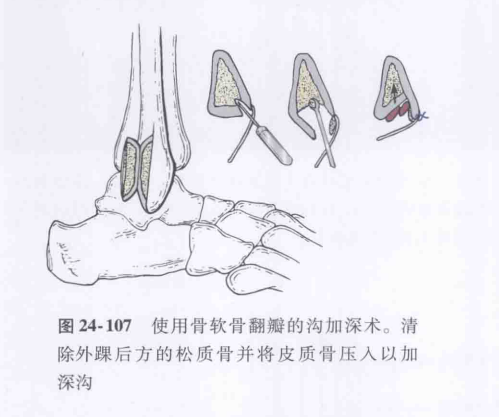

③外踝腓骨肌沟加深法;

图源:Coughlin M,Saltzman C,Anderson R,et al. 曼氏足踝外科学 [M]. 第 9 版. 唐康来, 徐林, 译. 北京: 人民卫生出版社,2015:1915.